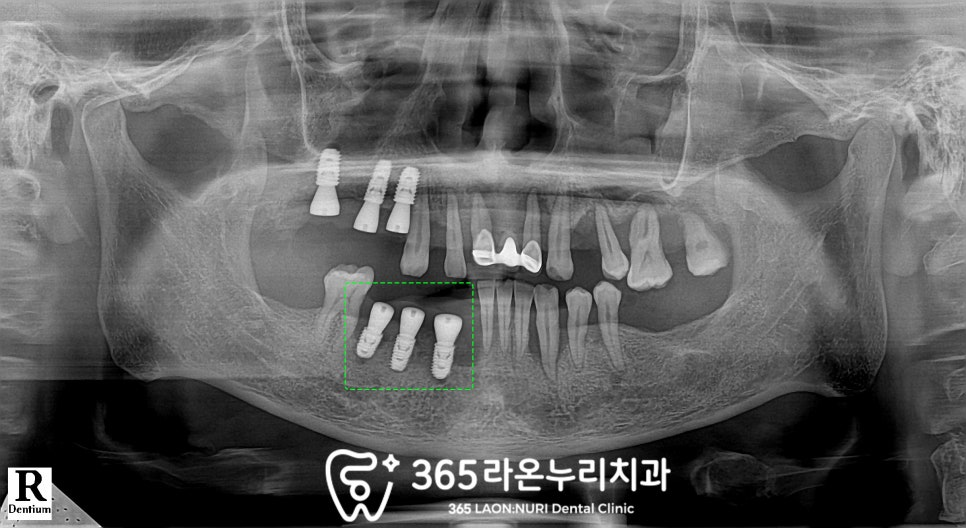

먼저 CT를 찍어

치조골 상태와 골소실 정도를

상세하게 살펴본 뒤

수명을 다한 이는 뽑습니다.

그리고 초기고정력을 받을 수 있는

최선의 위치를 찾아 식립을 하게 됩니다

픽스처는 환자의 치조골 상태에 따라

잇몸 안에 묻어두거나

힐링 어버트먼트라는

단추 뚜껑 같은 것을 달아

구강 내로 보이게 연결해두기도 하는데,

다행히 이 환자는

초기고정력이 조금은 확보되어

바로 힐링 어버트먼트까지 연결해 드렸습니다.